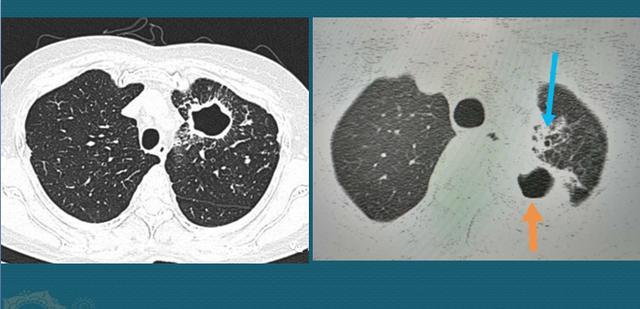

而肺结核则不然,它会繁殖,并且比癌细胞快很多倍,它适宜生长温度为37℃,正好是人体温度,增代时间大约为14-20小时。而且经气道吸入的结核菌原本就可以散布在多个角落,一起繁殖后代,造成病灶多发,所以我们看到结核球的周围经常有一些卫星灶,可以呈粟粒状、索条状、树芽征等多种表现,所以我们常说结核灶千变万化、无所不能。

下图是一位40多岁的男子,体检发现右肺肿块,周围有多发粟粒状、小斑片状影,提示结核球伴卫星灶,他比较紧张,选择手术切除,病例就是肺结核:

图片